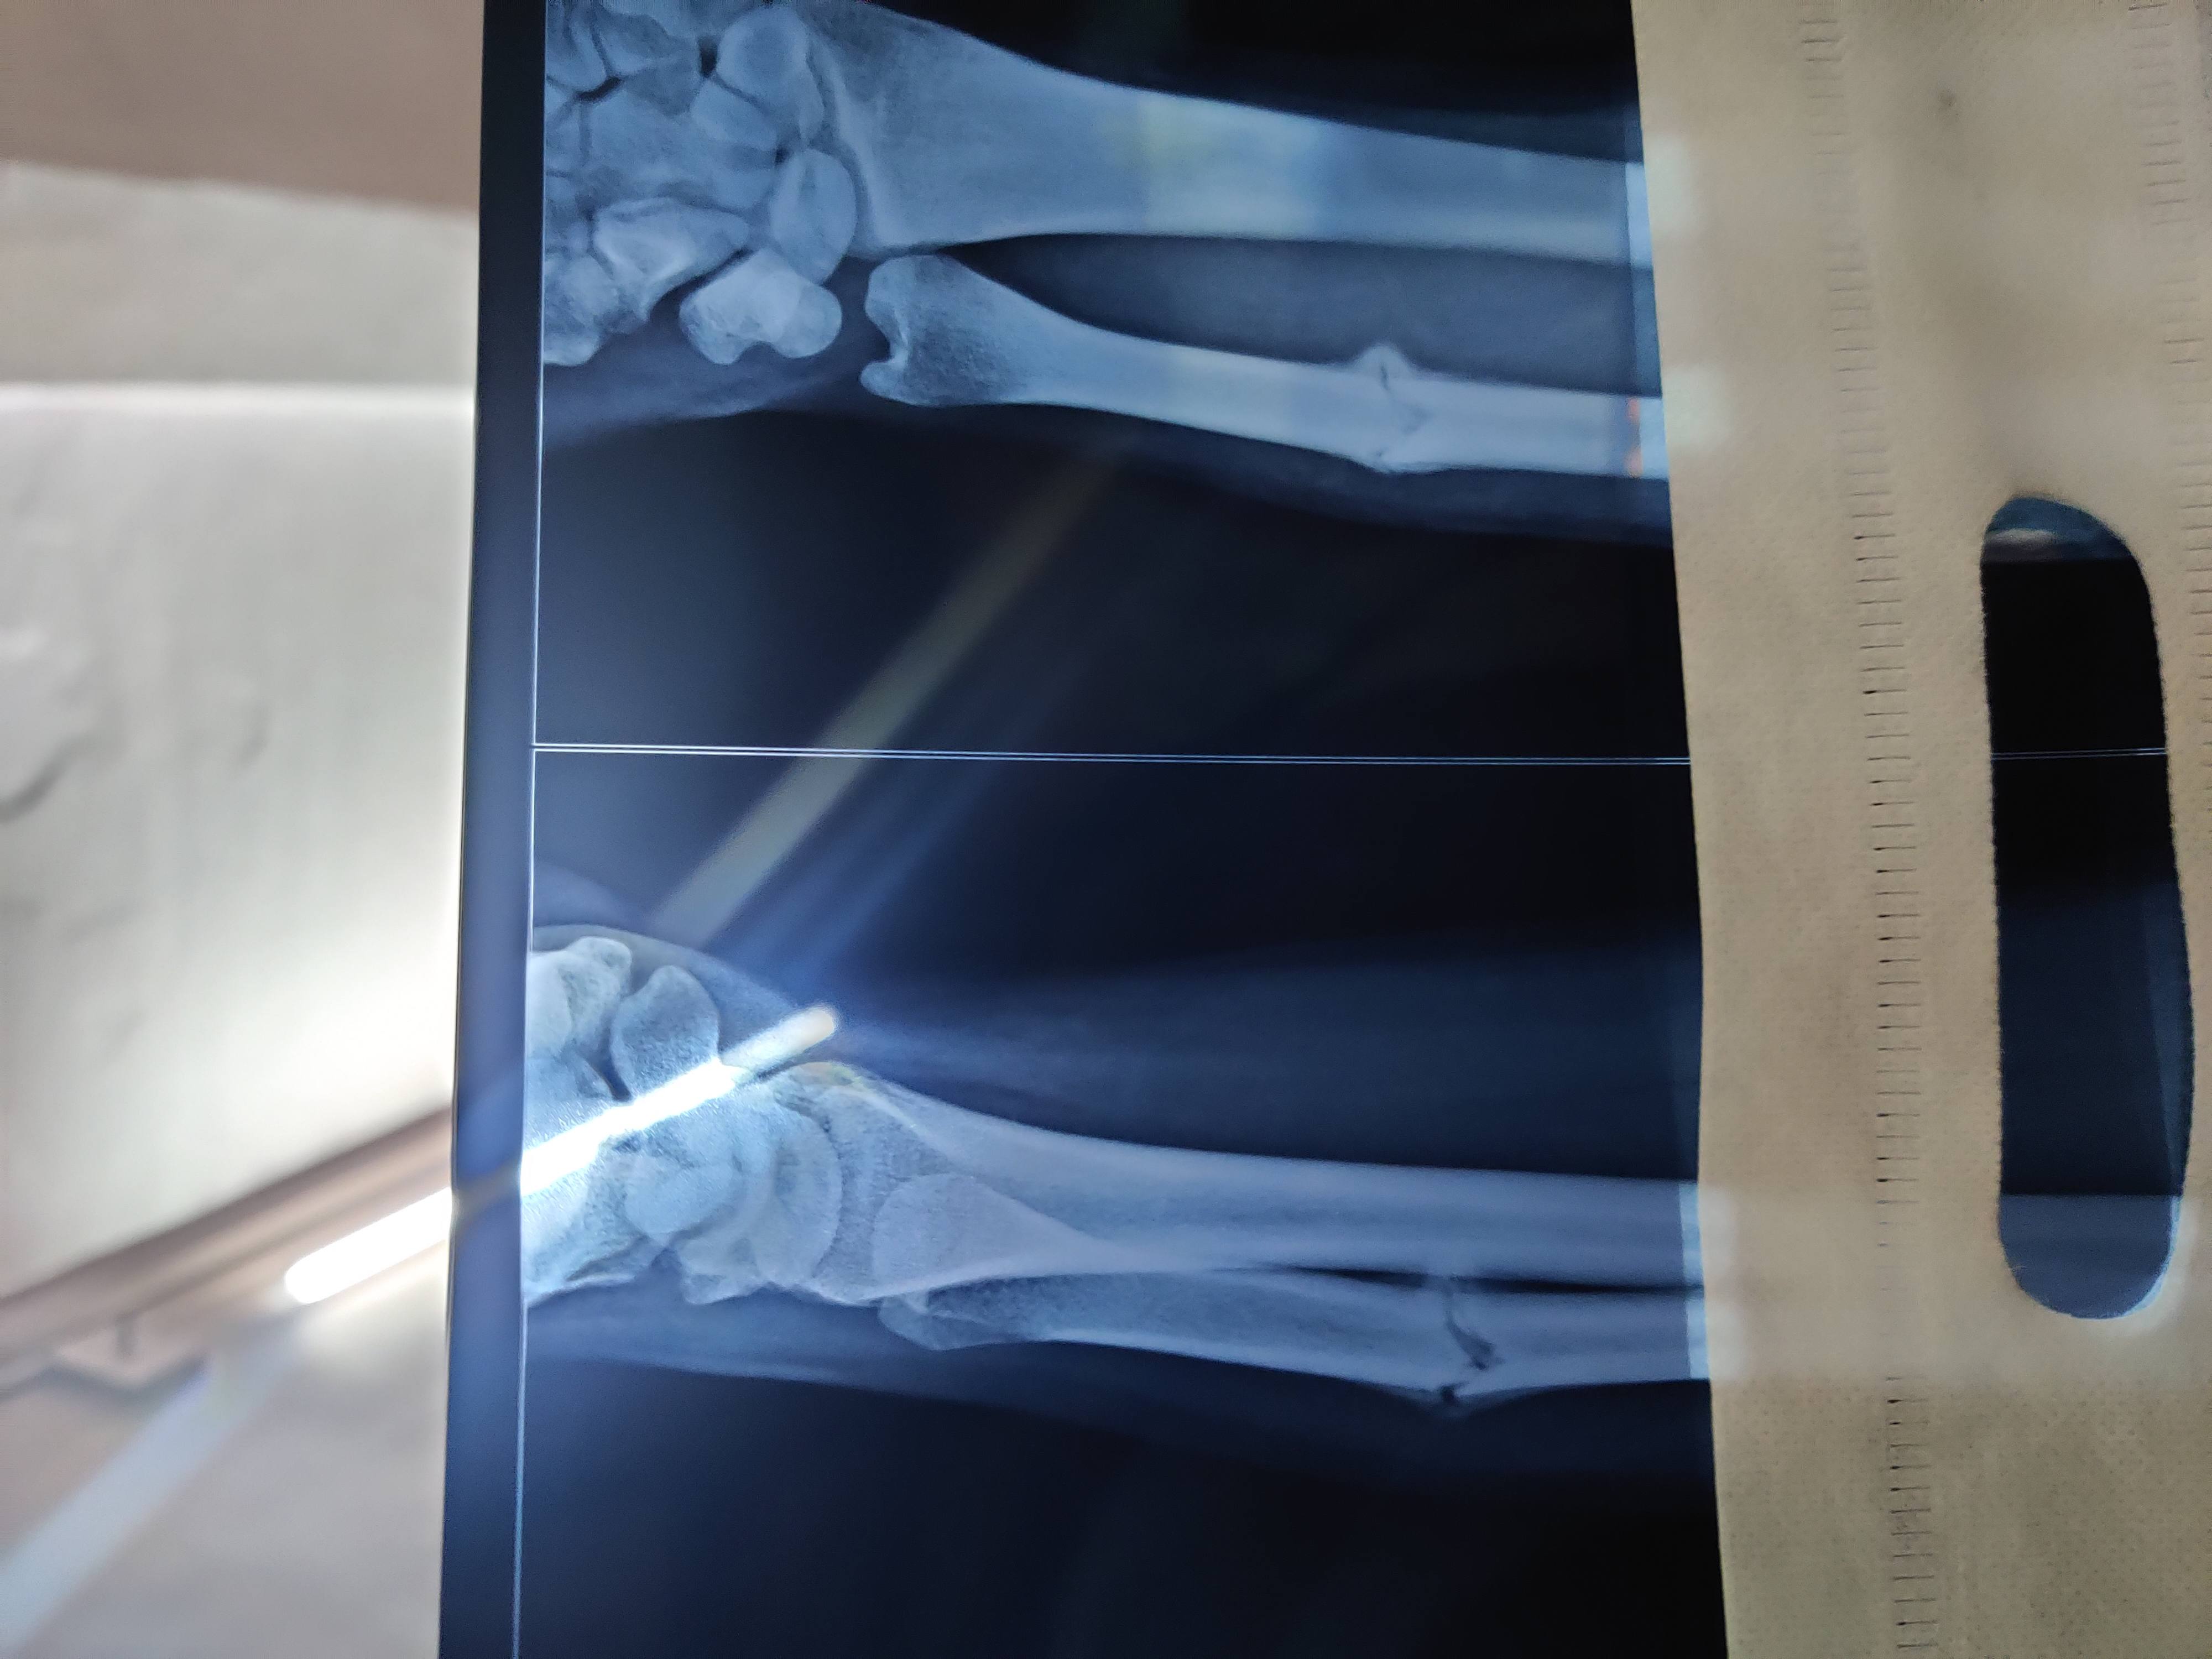

Hi sir this is my latest exray after 45 days bone has started healing. But i am still worried Because healing process is slow. It is still non union. I asked my doctor wheather surgery is required he said no can you please help i am getting very confused on this condition of my hand i am having no pain pain only occurs when I am doing pronation.

It's been 45 days and 15 days since my cast was removed. please help sir give me clarity